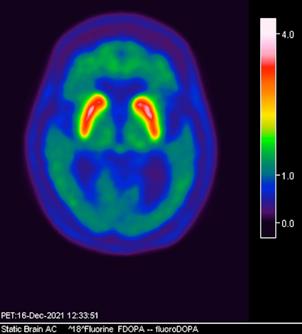

Femenino de 65 años, antecedente de hipertensión arterial de 20 años de evolución en control. Sin antecedentes familiares relevantes de enfermedades neurológicas. Acudió a consulta médica por deterioro progresivo en su capacidad motora y dificultades en las actividades diarias. Desde hace 2 años ha notado cambios en su marcha y en su habilidad para realizar movimientos finos con las manos principalmente del lado izquierdo, rigidez muscular, temblor en reposo siendo mayor del lado izquierdo y dificultad para iniciar y mantener el movimiento, especialmente al levantarse de una silla o al comenzar a caminar. Además, los familiares han observado que tiene una expresión facial inexpresiva y que su voz se ha vuelto más monótona. A la exploración física con expresión facial inexpresiva, temblor de reposo bilateral en manos de predominio izquierdo, rigidez muscular generalizada, más pronunciada en las extremidades superiores, bradicinesia evidente en la realización de movimientos finos de las manos, marcha festinante con pasos cortos y arrastrando los pies, reflejos osteotendinosos normales, no se observan déficits sensoriales. Se realiza adicionalmente la escala de Evaluación de la Enfermedad de Parkinson (UPDRS) con un total de 35 puntos, indicando moderada afectación de la enfermedad. Inicialmente se realiza una tomografía simple de cráneo, sin alteraciones estructurales, al no encontrar algún hallazgo se decide realizar posteriormente Resonancia Magnética Cerebral 1.5 Tesla: sin alteraciones estructurales significativas. Por este motivo y ante la alta sospecha clínica se realiza estudio de imagen molecular PET-RM con 6-[18F] FDOPA en equipo 3 Tesla en el cual se observa la disminución de la captación de la 6-[18F]FDOPA a nivel de putamen y caudado de predominio derecho evidenciando la degeneración dopaminérgica nigro presináptica a este nivel, con un patrón tipo 2 (Egg shaped) así como la mala definición de nigrosoma, estos hallazgos compatibles con enfermedad de parkinson. (Figura 1 y 2)

Actualmente, el diagnóstico del Parkinson se basa principalmente en métodos convencionales que incluyen: -Presencia de 2 de los 3 síntomas principales, con ausencia

axial fusionada de PET-RM 3T con

con disminución de la captación del radiotrazador a nivel de ambos putámenes en la región posterior y media de predominio derecho así como disminución en el caudado ipsilateral.

2. Reconstrucción tridimensional avanzada de imagen híbrida PET-RM 3T con 6-[18F]FDOPA observando disminución de la captación del radiotrazador a nivel de ambos putámenes en la región posterior y media así como en el núcleo caudado derecho.

Figura 3. Reconstrucción mediante imagen molecular de imagen híbrida PET-RM 3T con 6-[18F] FDOPA observando disminución de la captación del radiotrazador a nivel de ambos putámenes en la región posterior, media y anterior así como en ambos núcleos ca dados de predominio derecho.

Figura 4. Reconstrucción mediante imagen molecular de imagen híbrida PET-RM 3T con 6-[18F]FDOPA observando captación adecuada y conservada del radiotrazador en el cuerpo estriado (ambos putámenes y núcleos caudados) en un paciente negativo para enfermedad de parkinson.

En cuanto al campo de los estudios de imagen convencional y de laboratorio no existe alguna prueba que pueda confirmar la enfermedad. Sin embargo, las imágenes de diagnóstico por métodos de imagen molecular del tipo no invasivas, como la tomografía por emisión de positrones (PET) en conjunto con un resonador de 3 tesla (RM 3T), pueden respaldar el diagnóstico de un médico, actualmente éste método tiene una sensibilidad diagnóstica de 95.4%, especificidad 100%, valor predictivo positivo del 100% y valor predictivo negativo del 87.5%. (5,6)

La enfermedad de parkinson es una enfermedad neurodegenerativa con afectación principalmente motora (temblor, rigidez y acinesia) de sospecha y diagnóstico clínico, ante la limitación de los estudios de laboratorio y métodos de imagen convencional para el diagnóstico toman gran relevancia las técnicas de imagen molecular no invasivas como el PET-RM y PET-CT con 6-[18F]FDOPA que cuentan con gran sensibilidad y especificidad para respaldar o descartar el diagnóstico médico ante la sospecha de la enfermedad de parkinson y algunas otras enfermedades del trastorno del movimiento.